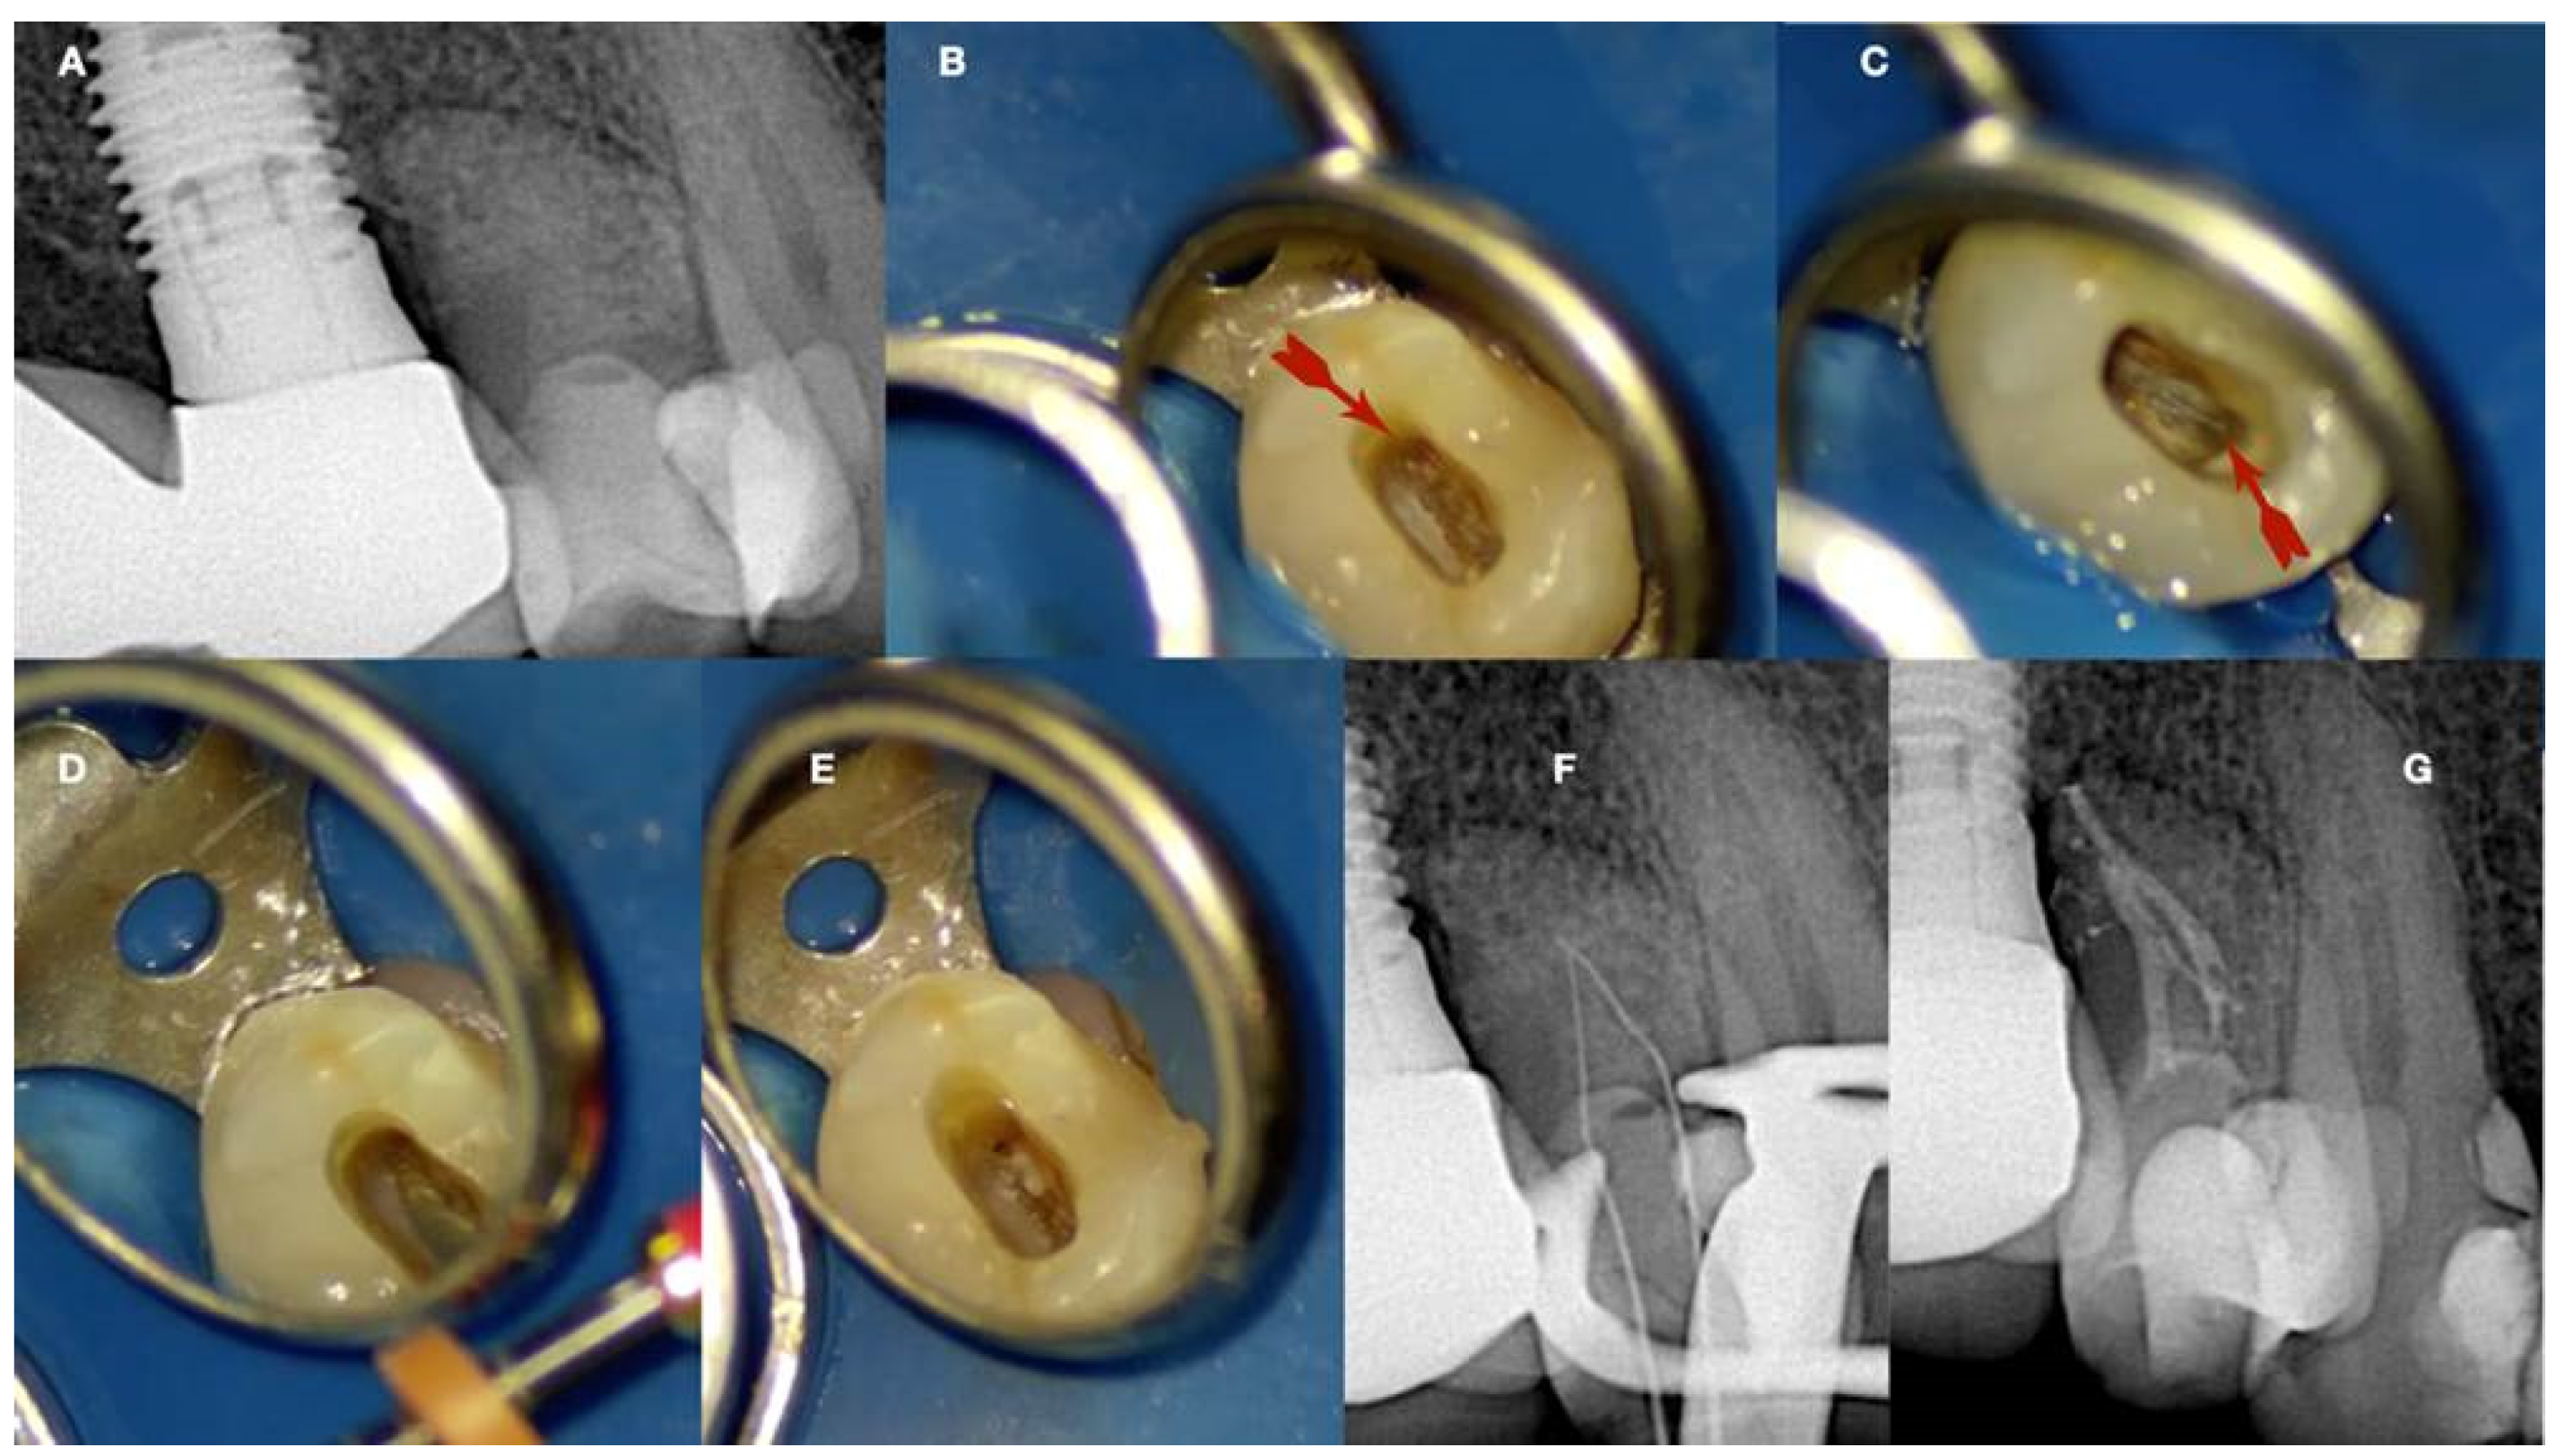

The static-guided technique involves the utilization of a guiding template in conjunction with cone beam computed tomography (CBCT) to aid in the localization of severely calcified root canals (Figure 15) [20,44,47,48,50]. This technique relies on the design of the guide, which is based on the anatomical features of the root canal and the surrounding tooth structures, obtained through CBCT images and either an impression or intra-oral surface scan, respectively (Figure 15) [51].

Figure 15.

(I) (A) Preoperative periapical radiograph of calcified maxillary central incisor diagnoses with apical periodontitis. (B) Preoperative clinical buccal view of the maxillary central incisors. (C) Preoperative cbct scanning of the maxilla. (D) Preoperative intraoral scanning of the maxilla. (E) Matching the CBCT scanning with the intraoral scanning and designing the guide in the codiagnostiX 10.5 software. (II) (A) Three-dimensional printed surgical guide with lateral windows to check the adaptation. (B) Intraoral fitting of the surgical guide. (C,D) Pencil marking of the access location point lingual and buccal view. (E) Access point mark to remove the enamel. (F) Fitting of the surgical guide and drilling the initial pilot hole. (G) Clinical palatal view of the guided access. (H) Intraoperative radiograph of the pilot drill (Steko bur). (I,J) Length determination and gutta-percha fitting radiographs. (K) Postoperative radiograph. (L) Two-year follow-up radiograph reveals healing (courtesy of Dr. Hugo Sousa Dias).

Specialized software, such as coDiagnostiX 10.5 (Dental Wings Inc., Montreal, Canada), is employed to superimpose CBCT data and 3D intra-oral scans, facilitating virtual planning of the access cavity [47,51]. Subsequently, a 3D virtual template is generated to produce the physical model of the endodontic guide, which guides the bur into the calcified root canal [47,51]. Static-guided access in cases of pulp canal obliteration (PCO) in anterior teeth has been previously documented in the literature and is described as a safe and predictable technique for minimally invasive access to calcified canals. This approach aids in preserving tooth structure, avoiding technical errors, and improving long-term prognosis [48,52]. Krastl et al. [53] were pioneers in describing the static-guided technique in vivo, specifically on a maxillary central incisor with PCO and apical periodontitis. Originally developed for implantology, this technology has been adapted for use in endodontics, surgery, and conventional access [54]. The static-guided technique involves accessing and locating root canals through a guiding template created via tomographic planning [48,52]. The guiding template sleeves direct the position of the access burs, enhancing perforation precision during access and ensuring adequate tomographic planning (see Figure 15). Ex vivo studies have demonstrated the high accuracy of the guided endodontics technique. Buchgreitz et al. [55] concluded that the mean distance between the drill path and the target was less than 0.7 mm, while Zehnder et al. [43] showed low deviations between planned and prepared access cavities, with mean angle deviations of 1.81° [56]. The accuracy of guided splints depends on various factors, including the type of support and study, technique used to produce the template, planning software, discrepancy between the drill and cylinder guide, degree of wear of the drill, and number of guides used [56]. However, guided templates are associated with limitations, such as inaccuracy, high economic cost, long therapeutic time, and potential complications [56].